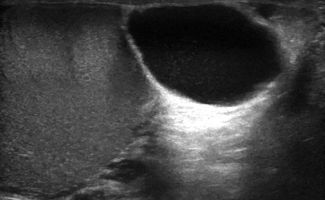

- Υδροκήλη

- Κύστεις